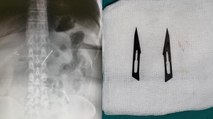

Sivas'ta yaşayan 12 yaşındaki genç kızın karın bölgesinde bulunan kavun büyüklüğündeki kist başarılı operasyonla çıkarıldı.